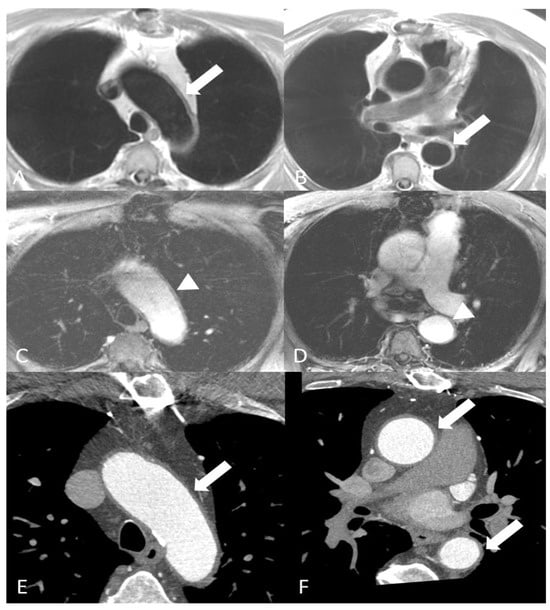

2.3.2. Eosinophilic Granulomatosis with Polyangiitis

- Fijolek, J.; Radzikowska, E. Eosinophilic granulomatosis with polyangiitis—Advances in pathogenesis, diagnosis, and treatment. Front. Med. 2023, 10, 1145257. [Google Scholar] [CrossRef] [PubMed]

- White, J.; Dubey, S. Eosinophilic granulomatosis with polyangiitis: A review. Autoimmun. Rev. 2023, 22, 103219. [Google Scholar] [CrossRef]

- Romero Gomez, C.; Hernandez Negrin, H.; Ayala Gutierrez, M.D.M. Eosinophilic granulomatosis with polyangiitis. Med. Clin. 2023, 160, 310–317. [Google Scholar] [CrossRef]

- Dennert, R.M.; van Paassen, P.; Schalla, S.; Kuznetsova, T.; Alzand, B.S.; Staessen, J.A.; Velthuis, S.; Crijns, H.J.; Tervaert, J.W.C.; Heymans, S. Cardiac involvement in Churg-Strauss syndrome. Arthritis Rheum. 2010, 62, 627–634. [Google Scholar] [CrossRef]